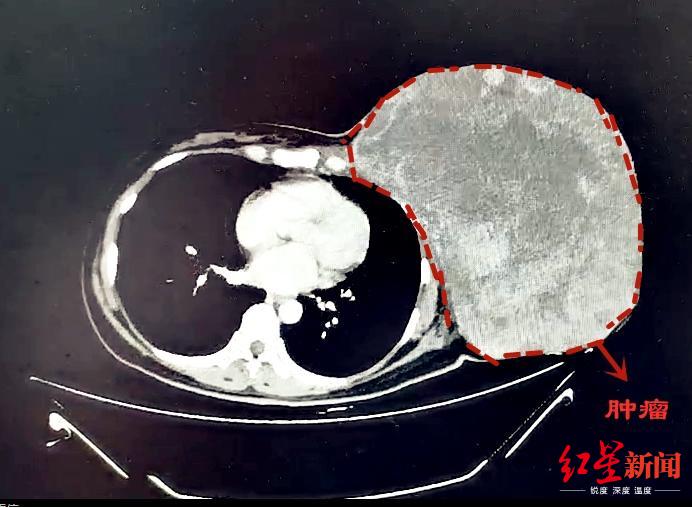

红星新闻从成都市第三人民医院了解到,一颗12斤“巨型”乳腺肿瘤,近日被该院多学科团队顺利摘除。

乳腺肿瘤已成为女性常见的疾病之一。然而,对于47岁的蒋女士来说,她的乳腺肿瘤只能用“心惊胆颤”来形容——直径约30cm、重达12斤!

CT影像

2年多前,蒋女士无意间发现左侧乳腺有一个包块,大约枣子般大小。因为没有疼痛等不适的感觉,她认为“可能问题并不严重”,未进行过系统化的治疗。不过,近半年来她发现包块不仅没有缩小,反而呈现出疯长的趋势。发展到现在,包块已经长到“篮球大小”,严重影响了外观,就连走路等生活日常都存在问题。

针对难点和风险,多学科小组进行了充分的准备及并制定应对措施。9月25日,经过4个半小时的手术精细剥离,将近12斤重的巨型肿瘤才被告捷完全摘除。后经病理诊断,确定为交界性叶状肿瘤。经过恢复,近日蒋女士顺利出院。